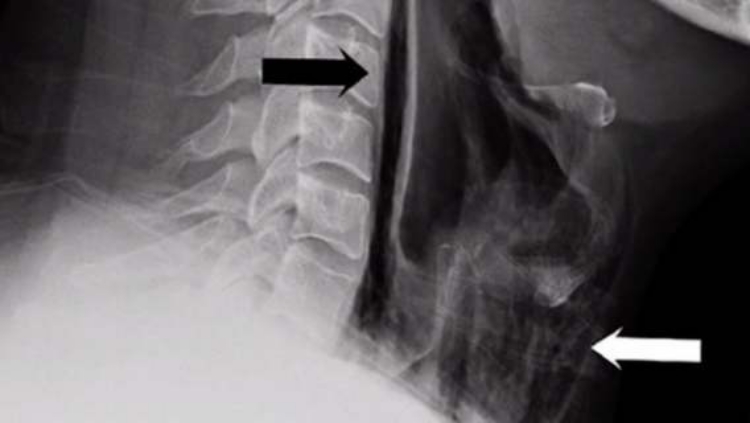

Dieser ungewöhnliche Kasus wurde auch in der britischen medizinischen Zeitschrift BMJ Case Reports beschrieben. Es stellte sich heraus, dass dieser junge Mann das Niesen praktisch sein ganzes Leben lang zurückgehalten hatte, einfach weil ihm Niesen in der Öffentlichkeit unangemessen erschien. Es dauerte jedoch eine Weile, diese bizarre Ursache der Beschwerden zu ermitteln. Zunächst stellten die Ärzte durch Palpation (Abtasten) fest, dass das Weichgewebe seines Halses erheblich geschädigt war. Auch beim Abhören waren seltsame Geräusche zu vernehmen, eine Art Knacken, Klicken. Auf dem Röntgenbild wurde dann die Ursache deutlich. Luftbläschen hatten sich in das Weichgewebe seines Halses ausgebreitet. Es kam also offenbar zu einer Perforation (Durchlöcherung) des Weichgewebes im Halsbereich infolge des übermäßigen Drucks beim Zurückhalten des Niesens, und Luft drang dorthin, wo sie nicht sein sollte. Im vorderen Halsbereich wurde ein ausgedehntes Emphysem festgestellt, also Luftbläschen im Weichgewebe und subkutanem Gewebe.